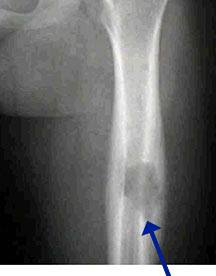

- May arise from any bone and any site within a bone (epiphyseal, metaphyseal, diaphyseal)

- Radiographically variable appearance: may appear benign (geographic) or malignant (permeative or moth eaten)

- Femur

- Humerus

- Curettage and bone grafting for long bones and weight bearing bones at risk for fracture